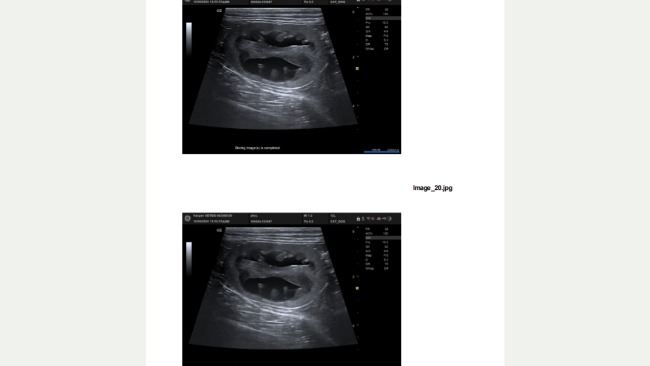

Ptyś na pierwszym płukaniu bajpasa i kontroli USG.